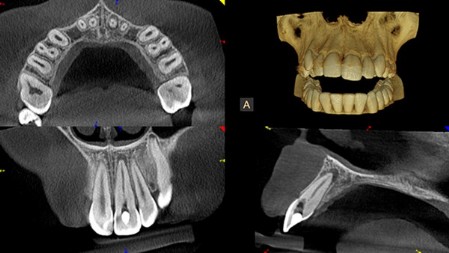

TC Cone Beam 3D (CBCT)

Con il termine TC Cone Beam (CBCT), si intende una macchina capace di scansionare le arcate dentali del paziente attraverso l’emissione di una dose molto bassa di raggi X fornendo immagini tridimensionali di altissima qualità delle ossa mascellari e dei denti. La tomografia Computerizzata Cone Beam 3D rappresenta pertanto il massimo raggiungibile nel campo della radiodiagnostica odontoiatrica.